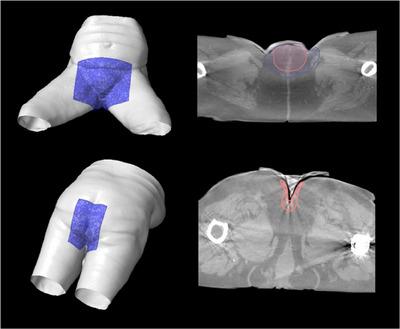

3D printed molds for bespoke bolus were created by exporting the DICOM structures of the bolus designed in the treatment planning system and manipulated to create a multipart mold for 3D printing. A silicone (Ecoflex 00-30) mixture is poured into the mold and cured to form the bolus. Molds for sheet bolus of five thicknesses were also created. A comprehensive FMEA was performed to guide workflow adjustments and QA steps.